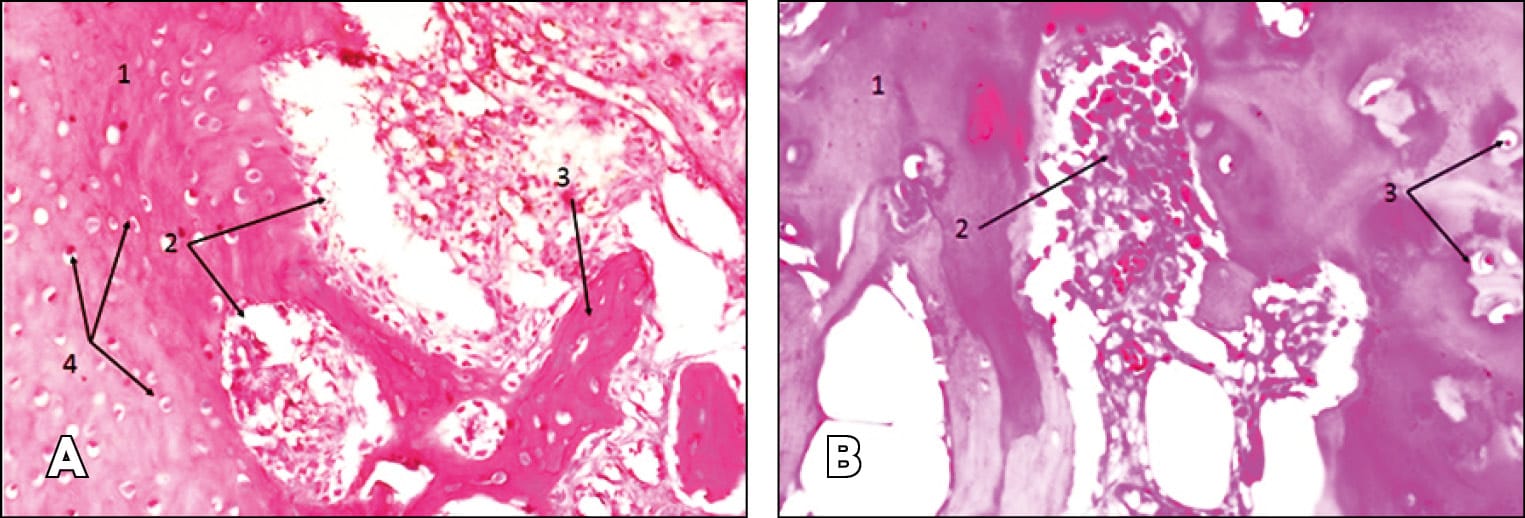

The analysis of histological sections yielded the following results: Paralytic dilated sinusoidal capillaries, intravascular stasis, and vascular edema were observed in all histological samples. In arthritis of steroid etiology, a large amount of lymphoplasmacytic and neutrophil infiltrate around sinusoidal-type vessels is observed (Figure. 2 B), eosinophilic leukocytes (Figure 4 A), necrotic granulomatous foci of inflammation, areas of hemorrhage, and giant multinucleated macrophages (Figure 1 B). During an acute inflammatory reaction, a large number of neutrophils, leukocytes, individual lymphocytes, and plasma cells were observed (Figure 2 A). In SA, multiple lymphoplasmacytic infiltrations, fibrosclerotic changes, multinucleated giant cells - Langhans-type cells, and granulomatous foci of inflammation accompanied by areas of hemorrhage were observed (Figure 1 A).

Destructive changes are more noticeable in osteoarthrosis. In the case of SOA, cartilage tissue samples show proliferation with foci of destruction (Figure 6 A). The same foci of destruction are evident against the background of normal cartilage tissue (Figure 7 B). In bone tissue samples, sequestra surrounded by a large number of neutrophils and leukocytes are noted, along with lymphoplasmacytic infiltration (Figure 5 A).

In SOA, we observe vessel wall destruction, lymphoplasmacytic infiltration, vascular fibrosclerotic changes, signs of hyperemia (numerous capillaries), fibrosis of adipose tissue, formation of bone sequestra, and multiple neutrophils and leukocytes (Figures 4 B, 5 A).

The histological analysis data we obtained somewhat confirm this. Cellular infiltration was detected in all groups. However, in patients with SSA and SSOA, it was relatively moderate. Similar results have been published in the literature on experimental arthritis [38] Kamarudin, T.A.; Othman, F.; Mohd Ramli, E.S.; Md Isa, N.; Srijit, D. Protective effect of curcumin on experimentally induced arthritic rats: detailed histopathological study of the joints and white blood cell count. EXCLI Journal 2012;11:226-236 – ISSN 1611-2156.. Neutrophils, leukocytes, lymphocytes, lymphoplasmacytic infiltration, paralytic dilated sinus-like capillaries, intravascular stasis, vascular fullness, and fibrosclerotic changes were found in all patients, but no significant differences between groups were found. The morphology of SA, regardless of etiology, is usually similar and is usually accompanied by significant destruction of all joint components. In the background of steroid administration, this process becomes more acute, especially noticeable when examining cartilage tissue. For example, in the case of SOA, cartilage specimens show proliferation with foci of destruction. In the case of SSOA, destructive foci, mainly with plasma cells, penetrated normal cartilage tissue in some areas (Figure 6B). SSOA is characterized by the formation of bone sequester, surrounded by a large number of neutrophils and leukocytes.

Thus, in steroid arthritis, the thickness of cartilage tissue was less compared to the other group, and the depth of the destruction site was greater. Getmanets, A.V. (2012) observed similar results in creating experimental arthritis in animals [26] Getmanets, A.V. Evaluation of the influence of experimental arthritis of the knee joint on the structure of the proximal epiphyseal cartilage of the tibia. Ukrainian morphological almanac - 2012. - Volume 10, No. 3. - P.149-152.. Comparing the data of morphological and microbiological studies, it can be suggested that the introduction of steroid preparations into the joint possibly initially causes changes in joint tissues that lead to cell necrosis of soft tissues with the development of an aseptic inflammatory process. This may occur as a result of disrupting POL processes, which intensify with the introduction of steroid preparations [39] T Ichiseki, A Kaneuji, S Katsuda, Y Ueda, T Sugimori, T Matsumoto. DNA oxidation injury in bone early after steroid administration is involved in the pathogenesis of steroid-induced osteonecrosis Rheumatology (Oxford) 2005 Apr;44(4):456-60. doi: 10.1093/rheumatology/keh518. Epub 2004 Dec 14.. With repeated intra-articular steroid injections, the percentage of such necrosis can significantly increase [40] Ozan Beytemur, Mustafa Fatih Dasci,Asiye Gök Yurttaş, Busra Yaprak Bayrak, and Ender Alagöz. The protective role of vitamins C and E in steroid-induced femoral head osteonecrosis: An experimental study in rats. Jt Dis Relat Surg. 2024 Jan; 35(1): 72–84. Published online 2023 Nov 2. doi: 10.52312/jdrs.2023.1405. M Suntiparpluachac et al. (2016) suggest that corticosteroids increase oxidative stress and alter the expression of genes such as cyclin-dependent kinase inhibitor 1A, growth differentiation factor 15, and c-Fos, which are involved in cell death and chondrotoxicity [41] M Suntiparpluachac , N Tammachote, R Tammachote. Triamcinolone acetonide reduces viability, induces oxidative stress, and alters gene expressions of human chondrocytes. Eur Rev Med Pharmacol Sci. 2016 Dec;20(23):4985-4992.. Pattaranatcha Charnwichai et al. (2023) also show that TA induces chondrotoxicity by enhancing oxidative stress and altering gene expression involved in cell death. The authors studied and compared histological analyses of materials obtained from patients undergoing knee joint arthroplasty. They showed that in patients who received intra-articular corticosteroid injections six months before the operation, a decrease in the thickness of articular cartilage was noted. The same decrease in articular cartilage thickness was noted in our study [42] Pattaranatcha Charnwichai, Rachaneekorn Tammachote, Nattapol Tammachote, Thiamjit Chaichana, and Nakarin Kitkumthorn. Histological features of knee osteoarthritis treated with triamcinolone acetonide and hyaluronic acid. Biomed Rep. 2023 Jun; 18(6): 40. Published online 2023 May 8. doi: 10.3892/br.2023.1623. Indirectly, the high number of negative microbiological analyses in patients in the acute phase of SSA - 66.7%, speaks to the primacy of aseptic cell necrosis.